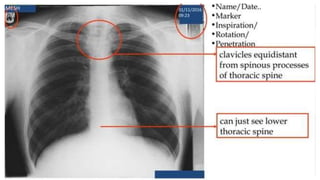

Rotation

• Patient rotation can be assessed by observing the clavicular heads

and determining whether they are equal distance from the spinous

processes of the thoracic vertebral bodies.

Rotation • Patient rotationcan be assessed by observing the clavicular heads and determining whether they are equal distance from the spinous processes of the thoracic vertebral bodies.